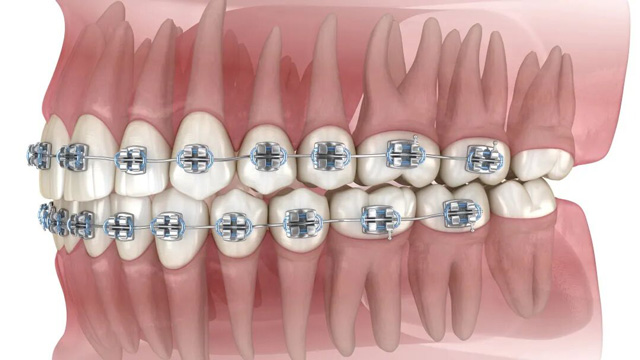

其实,智齿和正畸的关系,远比大家想象中密切——它就像口腔里的“隐形干扰者”,有时会悄悄破坏正畸效果,甚至让前期努力白费。

而正畸治疗期间需要定期复诊、调整矫治器。如果智齿反复发炎,不仅会让你承受疼痛,还会耽误正畸进度。

正畸是一场“持久战”,而智齿就是潜伏在暗处的变量因子,从正畸前评估到正畸后摘保持器,每个环节都很重要。作为深耕口腔正畸多年的老牌机构,新桥口腔推出系统化的“正畸全周期陪护服务”,从正畸方案定制到术后长期维养,全程守护,帮你规避风险、减轻顾虑,让正畸的每一步都更有保障。